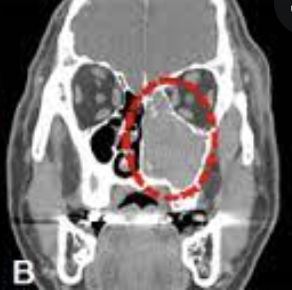

MRI 내용을 보니 코 안쪽이 공기로 차있어야되는데 저렇게 뭔가 가득 차있다고 제거를 해서 조직검사를 해야지 알 수 있다고 한다...

"반전성 유두종(Inverted Papilloma)" 라고 한다.

결국 물혹의 일종인데, 유두 같이 생겼다고 해서 유두종이라고 하고, 아래를 향하고 있다고 해서 반전성 이라고 지칭한다고 한다.

우연히 초기에 발견된 놈이니만큼 깔끔하게 제거는 했지만, 이놈이 재발확률이 매우 높아서 주기적으로 검사를 해보는게 좋겠다고 하신다.

이놈이 냅두면 점점 확장을 해서 뼈를 파고 들거나 심하면 코 밖으로 나올 정도로 커질 수도 있는데 초기에 발견되어서 제거는 잘할 수 있었다고 한다. 정말 다행이다 ㅠㅠ